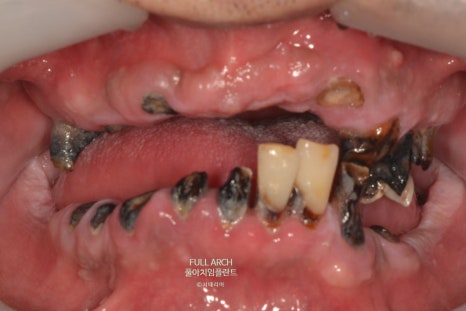

풀아치가 적합한 경우로는 다양한 복합적 치료가 불가능 하여 아래의 징후를 예를 들 수 있다.

광범위한 충치

잇몸질환으로 축적된 염증과 반복되는 감염으로 잇몸뼈를 상실한 경우

잇몸 퇴축으로 임플란트가 불가능한 경우

틀니사용이 불편한 경우

빠지거나 깨진치아가 여러개로 복합적인 문제들로 치료의 한계가 있는 경우